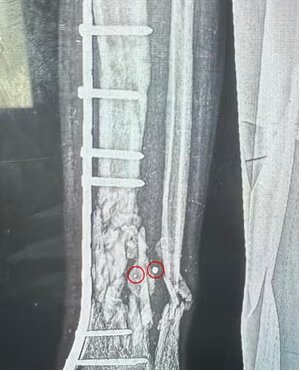

مارک پرلموتر، جراح ارتوپد از کارولینای شمالی، که در بیمارستان سیدوا کار می کرد گفت: کودکان در برابر هر گونه آسیب نافذ آسیب پذیرتر هستند، زیرا جثه کوچکتری دارند. قسمت های حیاتی آنها کوچکتر است و راحتتر از بین میرود. وقتی کودکان دچار پارگی رگهای خونی میشوند، رگهای خونی آنها آنقدر کوچک است که به سختی میتوان آنها را کنار هم قرار داد. شریان تغذیه کننده ساق، شریان فمورال، تنها به ضخامت یک رشته فرنگی در یک کودک است. خیلی خیلی کوچک است بنابراین ترمیم آن و چسباندن اندام بچه به آنها بسیار دشوار است.». تا حد زیادی شایع ترین زخم ها زخم های ورودی و خروجی یک یا دو میلی متری هستند. اشعه ایکس استخوانهای تخریبشده را نشان داد که در یک طرف آن یک سوراخ سوزنی، است و در طرف دیگر استخوانی است که به نظر میرسد یک تایر تراکتور از روی آن عبور کرده است. بچه هایی که ما آنها را عمل کردیم، اکثرشان از این مبادی ورودی و خروجی کوچک داشتند.

پرلموتر افزود: کودکانی که با چندین تکه از این ترکشهای کوچک زخمی می شدند، اغلب میمیرند و بسیاری از کسانی که جان سالم به در میبرند دست و پای خود را از دست میدهند. بیشتر بچههایی که جان سالم به در بردند، آسیبهای عصبی و عروقی داشتند که یکی از دلایل اصلی قطع عضو است. رگ های خونی یا اعصاب ضربه می خورند و یک روز بعد دست یا پا مرده است.